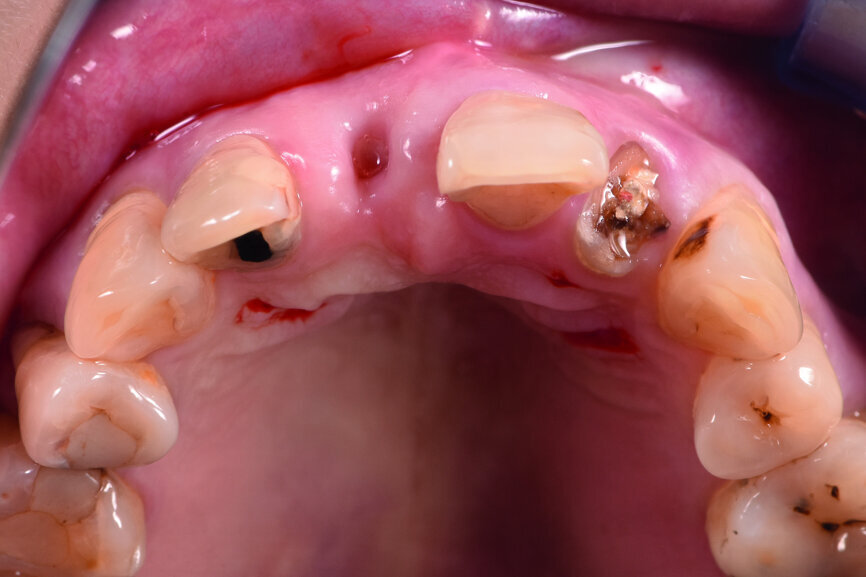

A 40-year-old female patient had sustained trauma to her anterior teeth caused by accidental syncope three weeks before. The clinical examination found that tooth #11 had been luxated; the crowns of teeth #12 and 21 had fractured, with the residual margin extending 3–5 mm below the gingiva and the teeth affected by Grade III mobility; and the crown of tooth #22 had fractured, with the residual margin at gingival level. There were no obvious abnormalities in the remaining teeth (Figs. 1–4). After excluding major systemic diseases, it was decided that she required fixed implant restoration with high demands regarding aesthetics and function.

Fig. 2: Pre-op occlusal view of the anterior teeth.